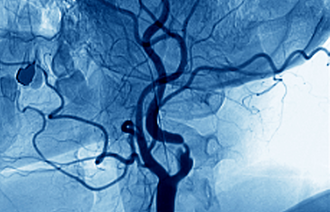

(Saken fortsetter under bildet.)

Kan skyldes tjukkere hjertemuskel

– Hvordan arter hjerteinfarkt seg som ikke skyldes tette blodårer?

– Årsakene er flere. Det kan for eksempel skyldes økt tykkelse i hjertemuskelen, som blant annet er en følge av høyt blodtrykk. Det fører til for lite surstoff.

Denne typen infarkt kureres ikke med utblokking.

Kvinner med hjerteinfarkt får i mindre grad spesialundersøkelser enn menn.

– På en måte er det naturlig, siden PCI ikke er nyttig for kvinner.